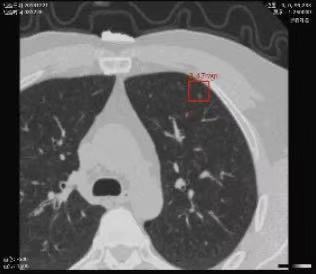

01.AI辅助影像识别与诊断

建立在医学影像诊断专家数据库基础上,通过将强化学习、深度学习等技术应用于医学影像,实现医学影像快速处理与病灶位置精确识别,予以医生诊断建议。主要应用于病理图像、眼底图像、放射、核磁等影像的快速诊断,降低医生诊断时间,减少误诊率,缓解医患矛盾;同时,探索自动影像获取技术,使一些基于实时信息的医学影像如超声图像、窥镜图像的智能识别诊断变为可能。